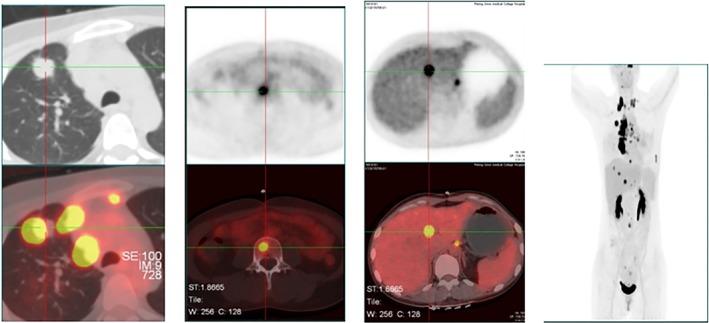

Common gene fusion of the ALK gene is fusion of the ALK tyrosine kinase area and the 5'end of EML4. Seventeen EML4-ALK fusion variants have been reported. Herein, we report a novel EML4-ALK variant detected by next-generation sequencing in a 36-year-old female lung adenocarcinoma patient who experienced disease progression after six months of alectinib treatment. Second generation sequencing revealed an EML4-ALK fusion variant in which intron 19 of EML4 was fused to exon 20 of ALK. This is the first case of EML4-ALK (E19: A20) fusion to be reported. Alectinib may show unsatisfactory therapeutic effects for this kind of ALK fusion.

ALK 基因的常见基因融合是 ALK 酪氨酸激酶区域和 EML4 的 5'端融合。已经报道了十七种 EML4-ALK 融合变体。在此,我们报告了一例通过下一代测序检测到的新的 EML4-ALK 变体,该变体存在于一名 36 岁的女性肺腺癌患者中,该患者在接受阿来替尼治疗六个月后出现疾病进展。二代测序显示 EML4 的内含子 19 与 ALK 的外显子 20 融合。这是首例报道的 EML4-ALK(E19:A20)融合。阿来替尼可能对这种 ALK 融合显示出不理想的治疗效果。